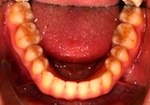

Patientin – 29 Jahre, Angle Kl. I, Invisalign für 9,5 Monate

Persistierender 52

(hier bereits entfernt)

12 war distal von 52 durchgebrochen

nachher